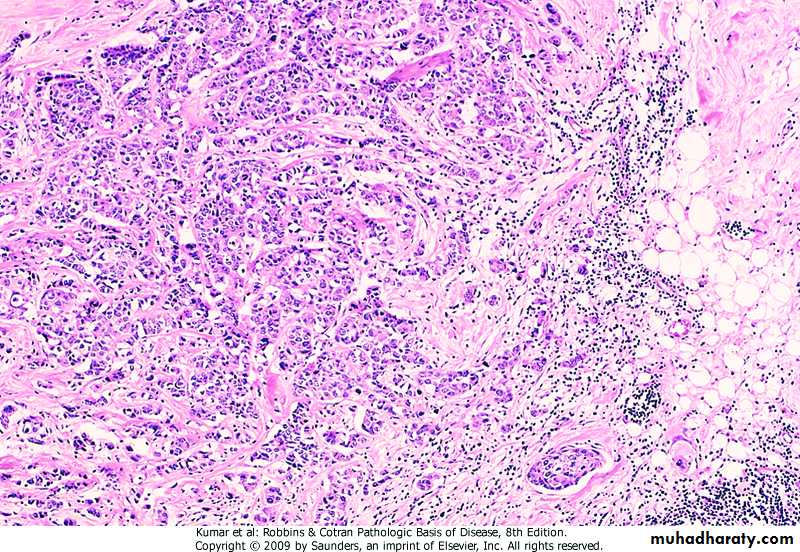

Anaplasia

.characterized by• -marked pleomorphism (variation in size & shape of cells & nuclei)

• -marked abnormal nuclear morphology (enlarged nuclei, prominent nucleolie, coarse chromatin, hyperchromasia)

• -mitoses (especially abnormal)

• -loss of cell polarity

• -other changes (tumor giant cells,

• necrosis)

Undifferentiated (anaplastic ) Neoplasm

Undifferentiated Neoplasm